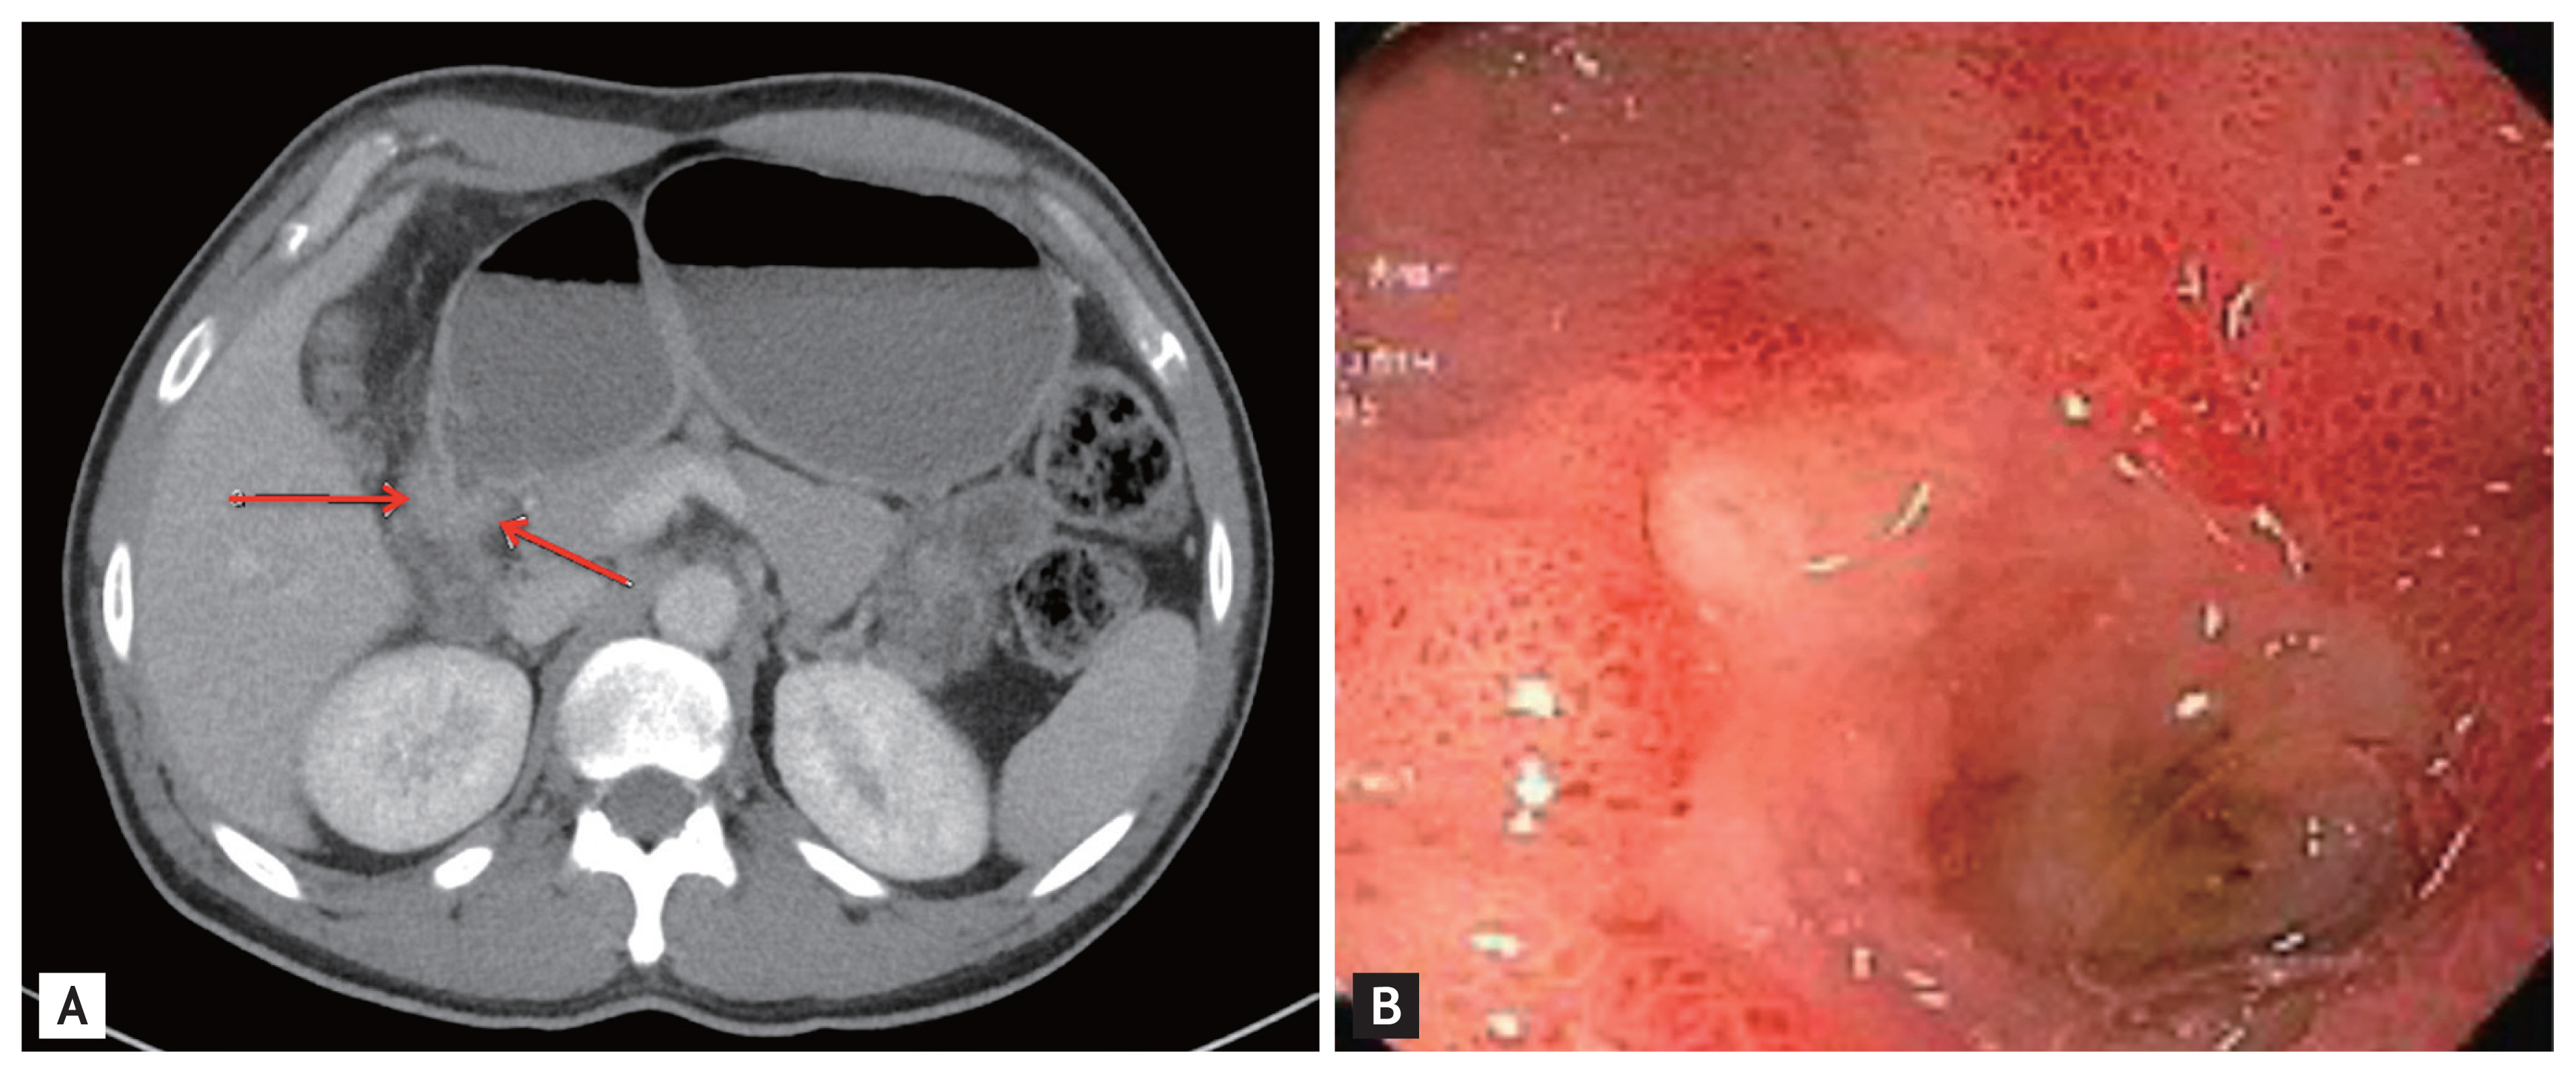

A previously healthy, 36-year-old Latino human immunodeficiency virus-negative man from the Southern United States with no recent travel history presented with one month of abdominal pain, nausea, vomiting, post-prandial emesis, and unintentional weight loss. He denied smoking, use of non-steroidal anti-inflammatory drugs, and history of Helicobacter pylori infection. Abdominal imaging showed a 2.2-cm gastric antral mass with evidence of gastric outlet obstruction (Fig. 1A). Upper endoscopy identified an ulcerated pyloric channel mass with raised edges causing gastric outlet obstruction (Fig. 1B). Biopsies from the ulcerated mass demonstrated necroinflammatory debris, round structures with well-defined boundaries, and underlying stroma with increased eosinophils. Periodic acid-Schiff (PAS) and Grocott’s methenamine silver stains were negative, and there were no signs of underlying malignancy. Repeat upper endoscopy with biopsies revealed similar findings. Despite conservative management with nasogastric tube decompression and intravenous proton pump inhibitor therapy, the patient’s symptoms persisted, and he underwent distal gastrectomy with loop gastrojejunostomy. By the third day after the surgery, the patient was tolerating regular diet. Final surgical pathology revealed coccidioidomycosis-associated chronic active gastritis and gastric ulcers. PAS stains showed large coccidioidomycosis spherules (up to 80 microns) with many endospores (Fig. 2). The patient’s symptoms had significantly improved post-operatively, and after the diagnosis of coccidioidomycosis was established, treatment was initiated with fluconazole 400 mg daily for 2 months. Outpatient follow-up was requested in the infectious diseases clinic. The diverse clinical manifestations of coccidioidomycosis make diagnosis particularly challenging. Gastrointestinal coccidioidomycosis is especially rare and there are scarce reports of cases presenting as small bowel obstruction or as gastric ulcers. In order to increase clinician awareness, we highlight a very distinctive gastrointestinal manifestation of coccidioidomycosis presenting as gastric outlet obstruction.

Figure 2

Periodic acid-Schiff stain from final surgical pathology highlighting large coccidioidomycosis spherules (up to 80 microns) with many endospores and evidence of chronic active gastritis.